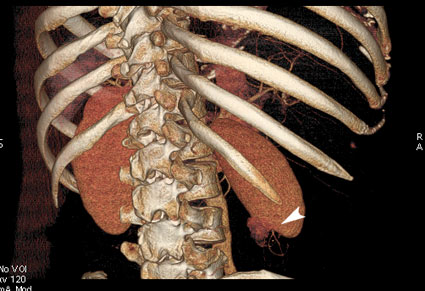

3D-реконструкция

se005.jpg (37.88 КБ) 998 просмотров